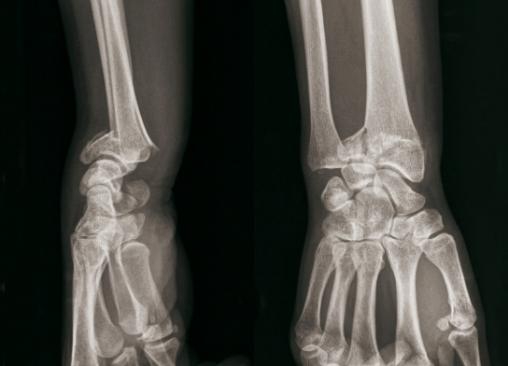

© Henry Coudane, Frédéric Éloy (La Revue du Praticien) Fracture articulaire complexe à déplacement postérieur. (À gauche) Radio de profil. (À droite) Radio de face.